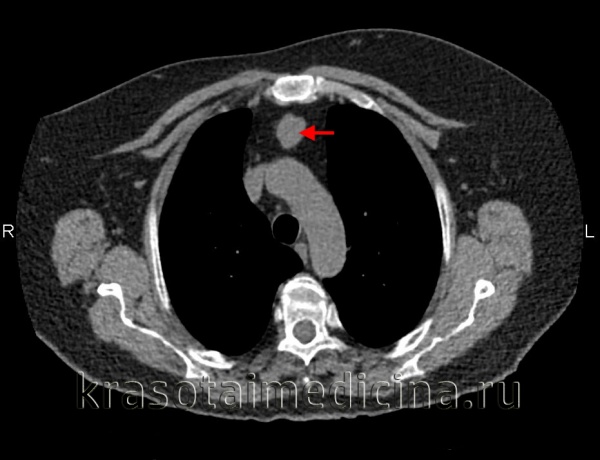

КТ ОГК. Массивное объемное образование верхнего средостения с объемным воздействием на трахею, исходящее из щитовидной железы.

- Рентгеновская диагностика. Комплексное рентгенологическое обследование в большинстве случаев позволяет четко определить локализацию, форму и размеры опухоли средостения и распространенность процесса. Обязательными исследованиями при подозрении на опухоль средостения являются рентгеноскопия грудной клетки, полипозиционная рентгенография, рентгенография пищевода. Данные рентгенологического исследования уточняются с помощью КТ грудной клетки, МРТ или МСКТ легких.

Обязательный перечень рентгенологических исследований включает рентгенографию грудной клетки, рентгенографию пищевода с контрастированием, компьютерную томографию. В большинстве случаев проведенное обследование позволяет установить локализацию рака средостения и распространенность процесса, заинтересованность органов грудной полости (легких, диафрагмы, аорты, грудной стенки). Уточнить состояние мягких тканей в зоне новообразования, выявить метастазы опухоли в лимфоузлы и легкие помогает МРТ.